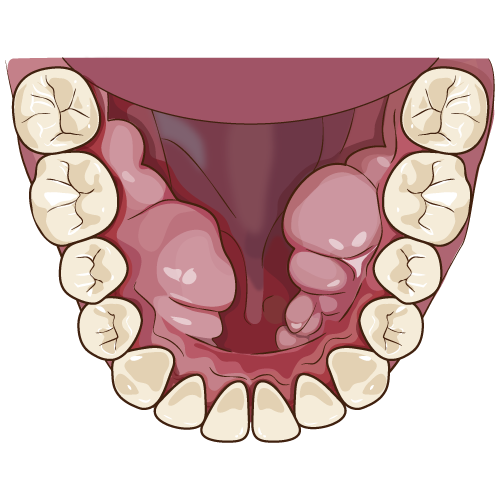

~部分入れ歯~

部分入れ歯(パーシャルデンチャー)は金属材料、義歯床用材料、人工歯科のプラスチック素材から構成されています。保険診療では材料とその適応範囲に制約があり、基本的には金属クラスプ(針金)を使用したクラスプデンチャーが適応です。保険での使用が認められている金属は、一部の金合金、金銀パラジウム、コバルトクロム合金、ニッケルクロム合金です。保険内の入れ歯(義歯)の利点は患者さんの経済的な負担が少なく、短時間での製作ができ、着脱できるので手入れがしやすいです。欠点はプラスチック素材で作られるため汚れやすく、違和感を感じやすくなります。金属クラスプ(針金)で歯を囲むようにして固定するので見た目がよくなく、金属クラスプ(針金)を固定する部分には段差が出ないように少し歯を削るため固定源になる歯は負担がかかります。自費診療では、審美的な人工歯など様々な形態、色調から自由に選択が可能です。制約のない自費診療は患者さんの口腔状態にもよりますが、色々な種類の材料から選択ができるため設計の自由がきき、患者さんの要望に対応したオーダーメイドの部分入れ歯(パーシャルデンチャー)を製作できます。発音や嚥下(えんげ)機能の妨げになる不要な厚みを薄くすることにより、違和感を軽減したり見栄えに配慮したクラスプ(針金)を設定したり審美的な人工歯や壊れにくいように強度の高い金属を使用する設計が可能です。保険適応とならない特殊な部分入れ歯(パーシャルデンチャー)の種類はコバルトクロム床義歯、純チタン床義歯(窒化処理のオプション有り)白金加金床義歯、アタッチメント義歯、コーヌステレスコープ義歯などがあります。

アタッチメント義歯は金属クラスプ(針金)を歯と一体化にした精密義歯(入れ歯)です。一体化することによって保険の入れ歯(義歯)よりも小型にすることができます。一般的な保険の入れ歯(義歯)は金属クラスプ(針金)だけで固定します。金属クラスプ(針金)だけでは不安定なため義歯床材料(プラスチック部分)を大きくして安定するように製作されています。そのため入れ歯(義歯)装着時の際、お口の中での違和感が強くなり発音機能が悪くなり、食事がしにくくなります。アタッチメント義歯の欠点は入れ歯(義歯)を固定する時に歯を削る必要がありますが、入れ歯(義歯)と歯がしっかりと固定されるため簡単には外れにくく、装着時の違和感が少ないです。審美性(見た目の美しさ)が回復し、咀嚼機能もよく食事している時にアタッチメント義歯は外れにくく、強く噛むことが可能という利点を持つ入れ歯(義歯)です。